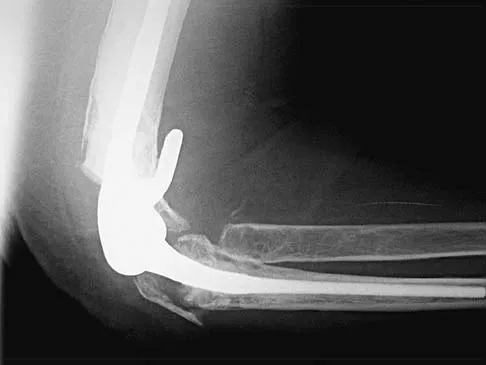

Question 32High Yield

A 54-year-old woman sustained an elbow injury 3 months ago that was treated with open reduction and internal fixation. She now reports pain and limited elbow motion. Radiographs are shown in Figures 10a and 10b. Treatment should now consist of

Explanation